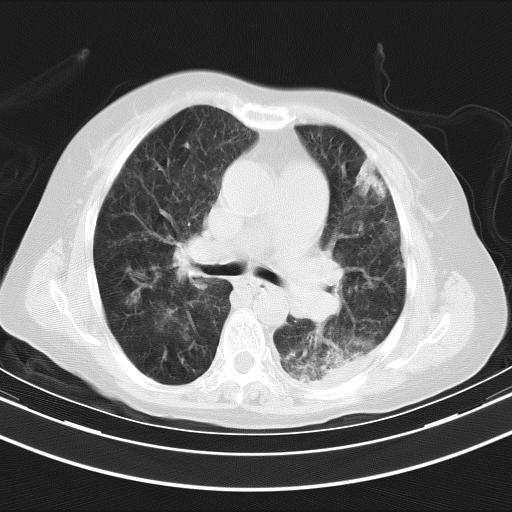

老年女性,嗜睡3天,意识模糊。轻咳,无发热。

两肺慢支炎伴感染,左侧胸腔积液。纵膈及双侧肺门淋巴结肿大建议复查。

双肺多发淡片影,毛玻璃影,,支持支气管肺炎,,建议血气找原因,,嗜睡是否肺性脑病?有没有慢支病史?

双肺炎症,建议抗炎治疗后复查,见过几个老年肺炎病例,没有发烧、咳嗽症状,直接以昏迷就诊。

1)两肺感染性病变;建议抗炎治疗后复查。2)纵隔淋巴结肿大。3)左侧胸腔积液。